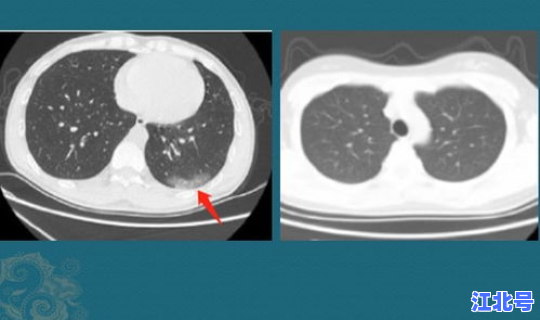

近日,有三名回国人员从重庆入境时被检测出了新冠病毒,再一次敲响了我国防止输入型新冠病毒的警钟 ,根据中国疾控中心发布的消息,这三人感染的病毒均为印度流行的变异病毒,三人在旅途过程中有做好防护 ,在印度的多次核酸检测结果均为阴性,也没有体温的异常,但胸部CT的结果显示出了感染性病变 ,因此被确诊为新冠病例。